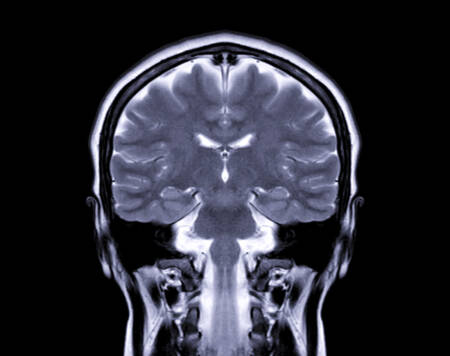

Combinando ressonância magnética e inteligência artificial, os cientistas identificaram que o álcool pode antecipar danos neurais que normalmente só apareceriam décadas depois, levantando um sinal de alerta especialmente para jovens que iniciaram o hábito ainda na adolescência.

A pesquisa avaliou 58 adultos com idades entre 22 e 40 anos, a maioria com histórico de consumo alcoólico desde a juventude. Após responderem a questionários sobre hábitos de bebida, os participantes foram submetidos a testes de flexibilidade cognitiva e exames de ressonância magnética em 3D.

A partir das imagens cerebrais, algoritmos de machine learning calcularam a chamada Diferença de Idade Predita (DAP), uma métrica que estima o quanto o cérebro aparenta ser mais velho do que a idade real da pessoa. Quanto maior o consumo de álcool, maior foi a discrepância — ou seja, maior o envelhecimento cerebral.